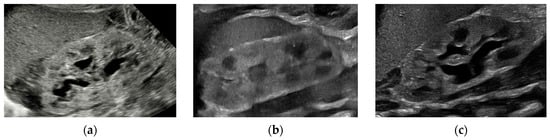

On day-of-life 1 (DOL 1), the baby was anuric and renal US demonstrated mild unilateral hydronephrosis (Figure 2a). Initial laboratory tests revealed elevated serum creatinine levels, indicating impaired renal function A 3.5-Fr urethral catheter was placed for temporary diversion, draining a high-volume output of 45 mL (4 mL/kg/h). On DOL 2, an abdominal X-ray confirmed a double-bubble sign, and the patient was taken to the operating room for end-to-side repair of type III proximal DA. His indwelling catheter was replaced with a 4.7-Fr × 10 cm double-J stent, advanced via the urethra due to poor drainage from the initial indwelling catheter. There were two episodes of urethral stent dislodgement during diaper changes, each resulting in a spike in creatinine and poor urine output (Figure 1). These dislodgements posed significant challenges in maintaining adequate urinary drainage and further necessitated close monitoring of renal function.

Figure 2.

Left sagittal ultrasound of the kidney at (a) day-of-life 1 with mild hydronephrosis, (b) day-of-life 10 with urethral stent in situ and resolved hydronephrosis, and (c) day-of-life 18 with new, mild hydronephrosis after stent removal.